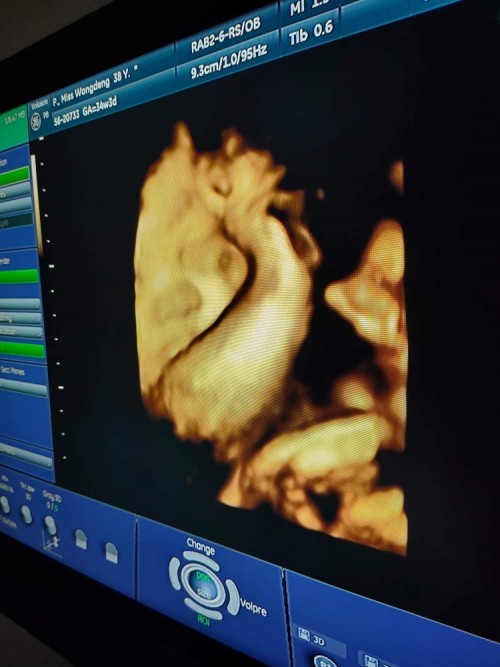

มาอวดรูปตอนซาวด์กันหน่อยค่ะ แม่ๆกำหนดคลอดเดือนไหนบ้างคะ